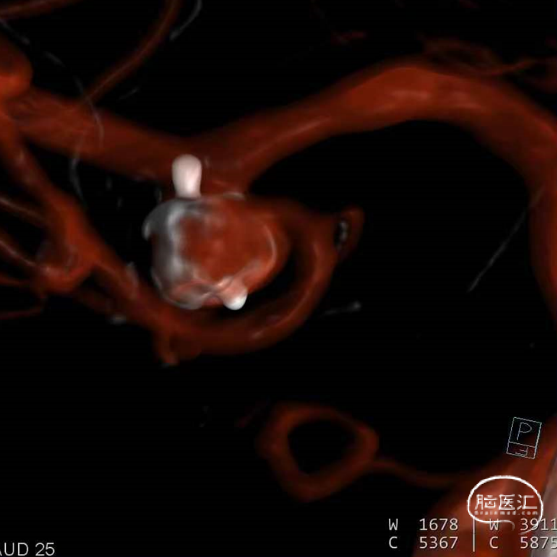

经测量可得动脉瘤宽度平均值为7.0mm,动脉瘤高度为5.18mm,选用WEB™ SL 8*4。

WEB™经由VIA™微导管送入动脉瘤瘤腔并完全释放。术后即刻造影显示WEB™尺寸合适,贴壁良好,分支等血流通畅。解脱后再次造影,可见动脉瘤瘤腔内有明显造影剂滞留。

术后3个月随访,WEB™完全栓塞,动脉瘤完全闭塞。